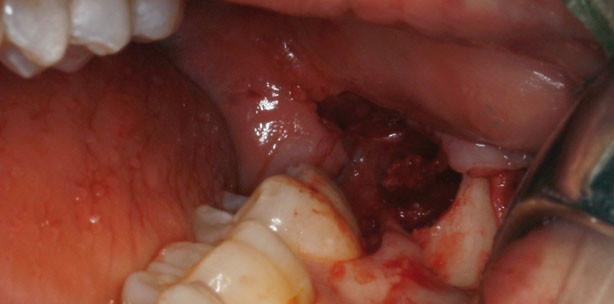

Die in diesem Artikel beschriebene Schnittführung verzichtet auf die retromolare Inzision (Abb. 1) und besteht aus einer einzigen Inzision. Diese wird ausgehend vom distobukkalen line angle des Zahnes 7 senkrecht und geradlinig auf Os ins Vestibulum geführt. Mit einem Raspatorium wird dann strikt auf Os ein vollschichtiger Lappen nach distal, retral und lingual präpariert (Abb. 2–11). Zur verbesserten Übersicht können bei Bedarf die Inzision nach mesial sulkulär fortgesetzt und die Lappenpräparation auf den Zahn 7 ausgedehnt werden (Abb. 12–15). Nach Osteotomie und Zahnentfernung erfolgt die Reposition des Lappens in seine Ausgangslage. Mit zwei bis vier Einzelknopfnähten erfolgt ein komplikationsloser Nahtverschluss auf knöcherner Unterlage (Abb. 9 und 15).